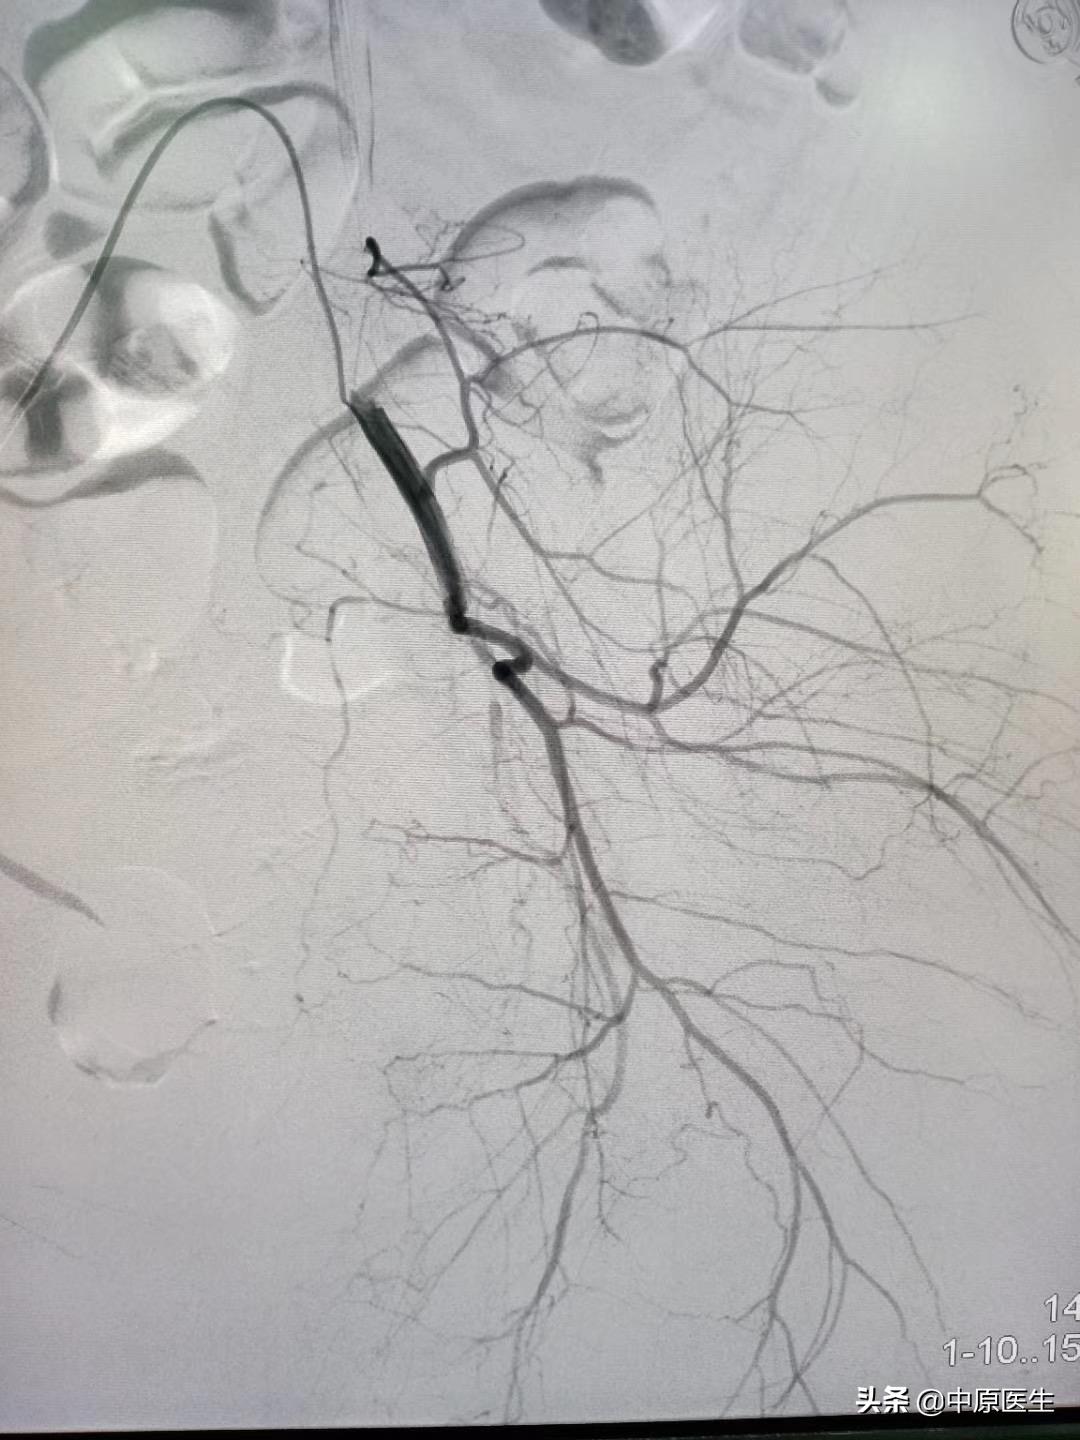

我处理好门诊事宜,十点赶往导管室,按标准预防做好术前防护、术前准备工作。在导管室的护士、技师等积极配合下,手术顺利开展,造影显示左侧子宫动脉近宫颈处有一破口、形成假性动脉瘤,假性动脉瘤破溃,造影剂快速流入宫腔内(相当于找到了河流的决口处);紧急用生物胶栓塞该破口及其远、近端血管(相当于堵住了决口及其上下游,上游流不进来、下游的倒灌不了),复查造影未见造影剂外渗、动脉瘤、静脉早显等异常血管影(成功止血)。然后选择双侧髂内动脉各分支造影未见明显异常血管,再予右侧子宫动脉栓塞。半小时顺利完成手术,病人生命体征平稳。安全送回病房,继续药物治疗。

子宫动脉栓塞术是治疗妇产科疾病常用技术,美国前国务卿赖斯曾因子宫肌瘤行子宫动脉栓塞术。具体操作是在DSA等影像设备引导下,局部麻醉,从大腿根部的股动脉穿刺、约一米粒大小的针眼,送入直径约2mm的导管到达病灶供血动脉,利用栓塞颗粒、微弹簧圈、生物胶等栓塞材料阻断病变的供血血管,达到止血和/或使病变缺少营养,继而坏死、萎缩缩小。DSA的火眼金睛可使出血动脉和肿瘤供血动脉无处可逃,这样的栓塞治疗,具有疗效确切、创伤小、无切口、恢复快、复发率低、可保留子宫的优点,这样的治疗,可以让女人保留原装子宫、做完美的女人!(本号总顾问梁宝松教授,1984年毕业于河南医科大学本科,河南省人民医院消化内科主任医师 教授)